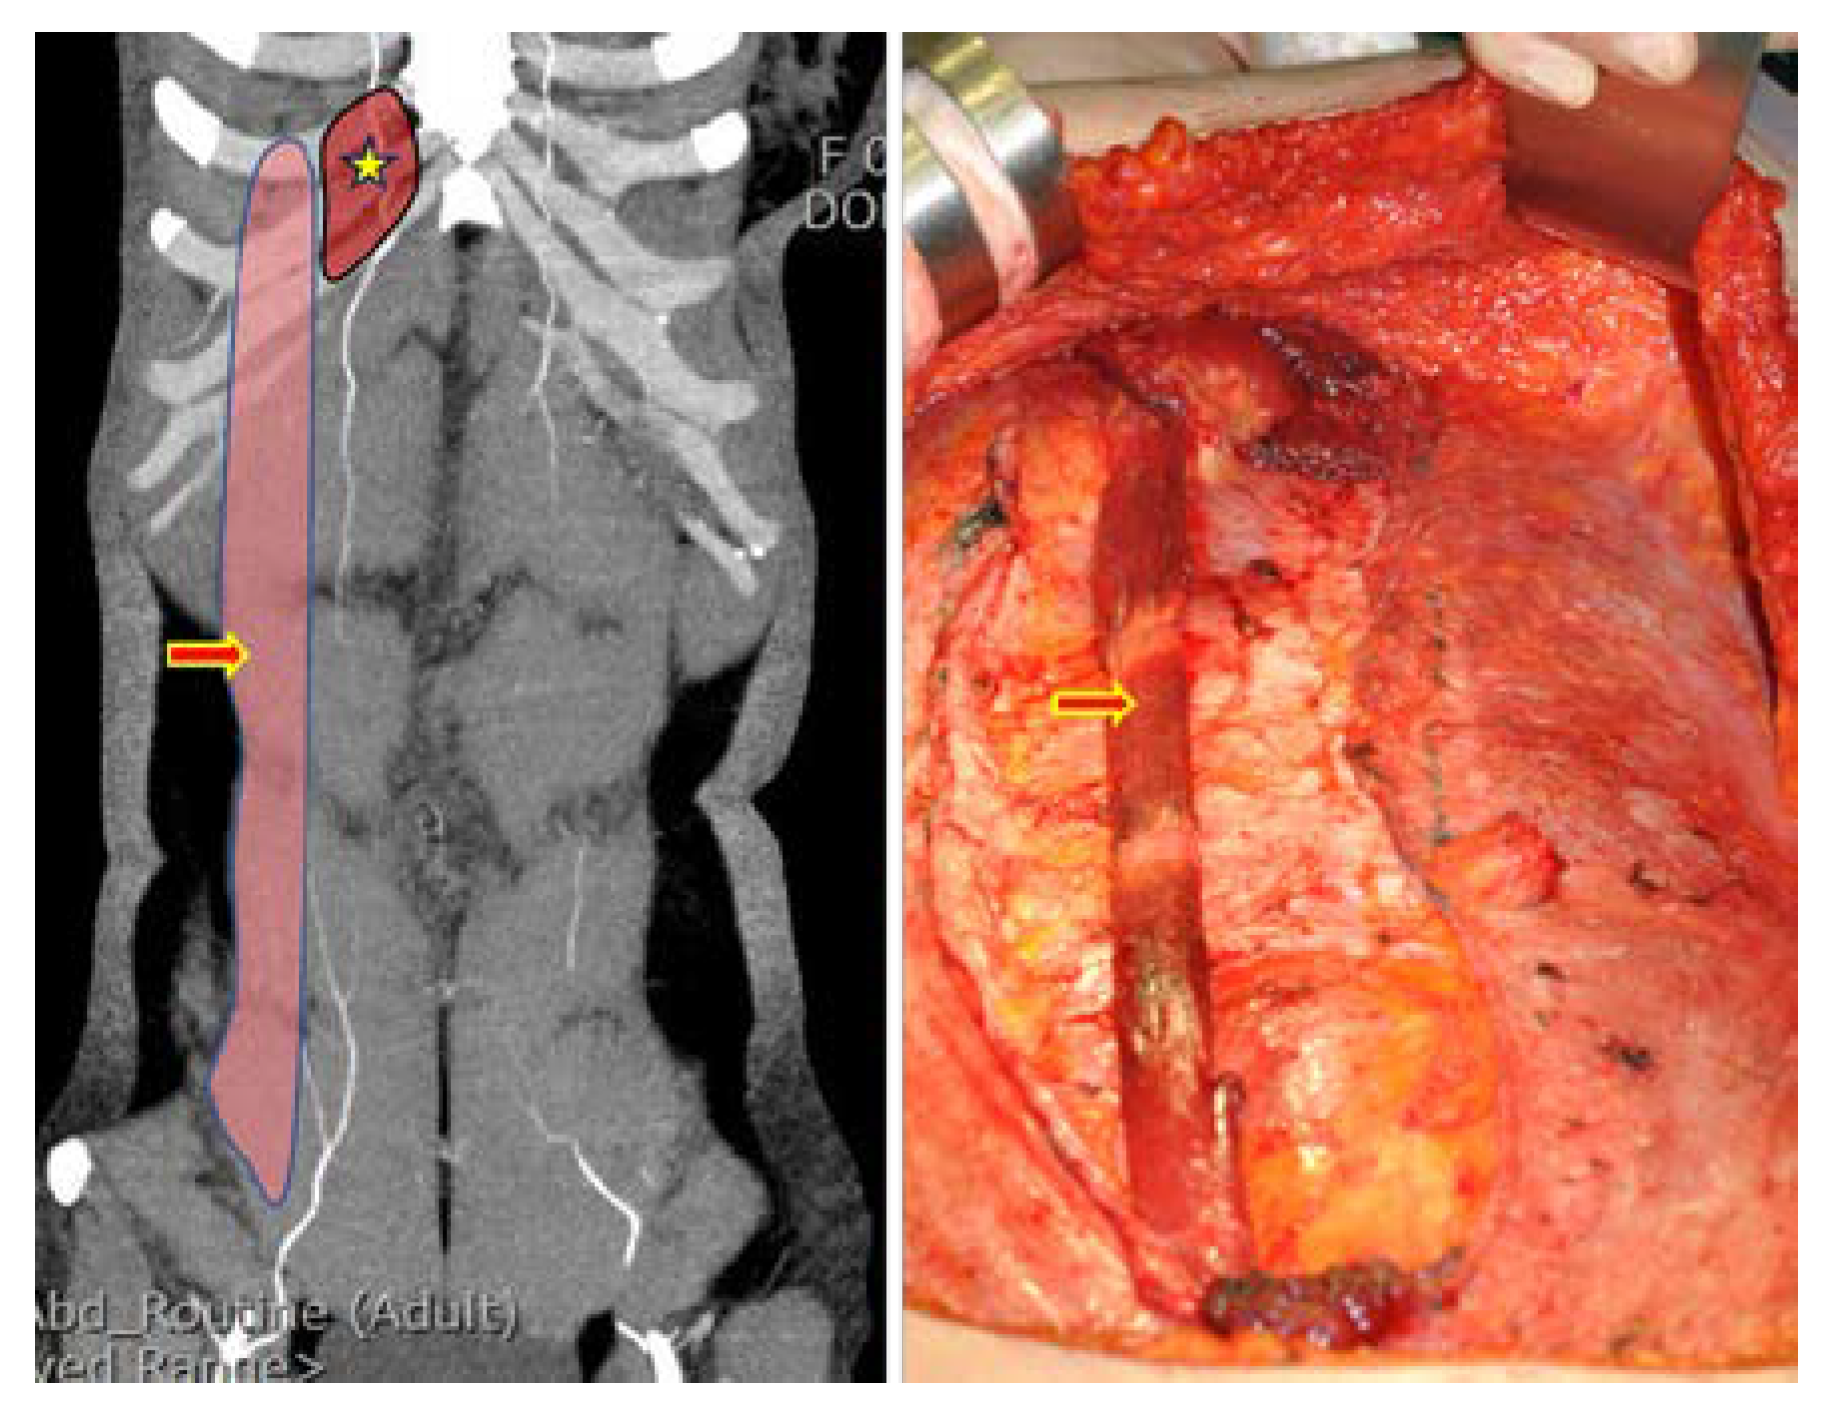

2.2.3. Partial Removal of Rectus Abdominis Muscle Inserting into Ribs and Flap Insetting